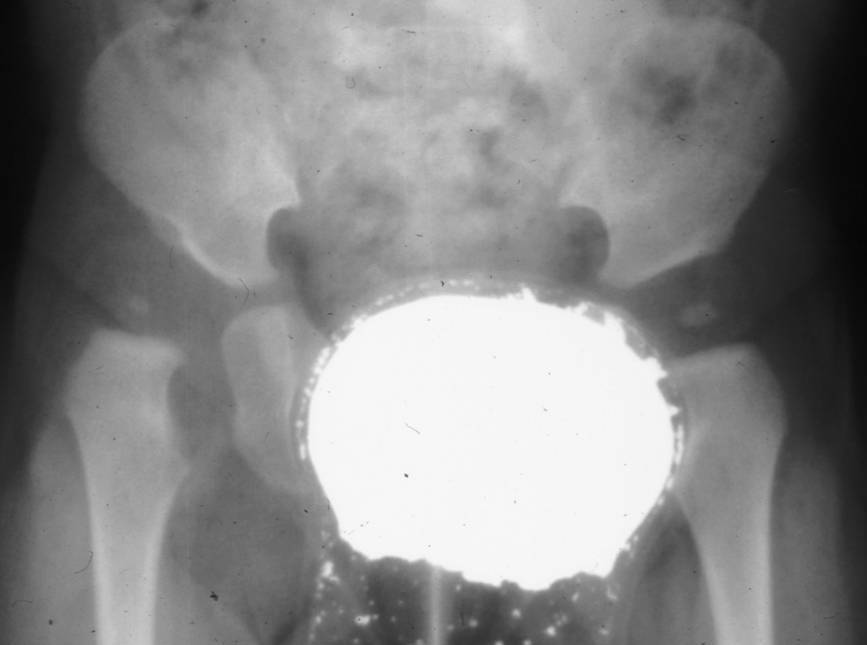

La radiografia è un esame di secondo livello nello studio della DCA. È limitata allo studio dell’osso senza evidenziare i tessuti molli, per questo è riservata nei pazienti dai 4-6 mesi d’età, o che sono già in trattamento.

La centrazione viene ottenuta attraverso il confezionamento di gessi pelvi-podalici modellati in anestesia generale, preceduti o meno da una trazione progressiva dell’arto inferiore.